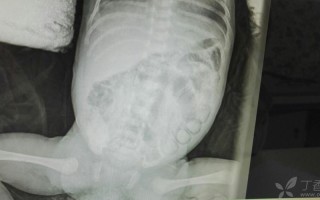

(图片来源网络,侵删)